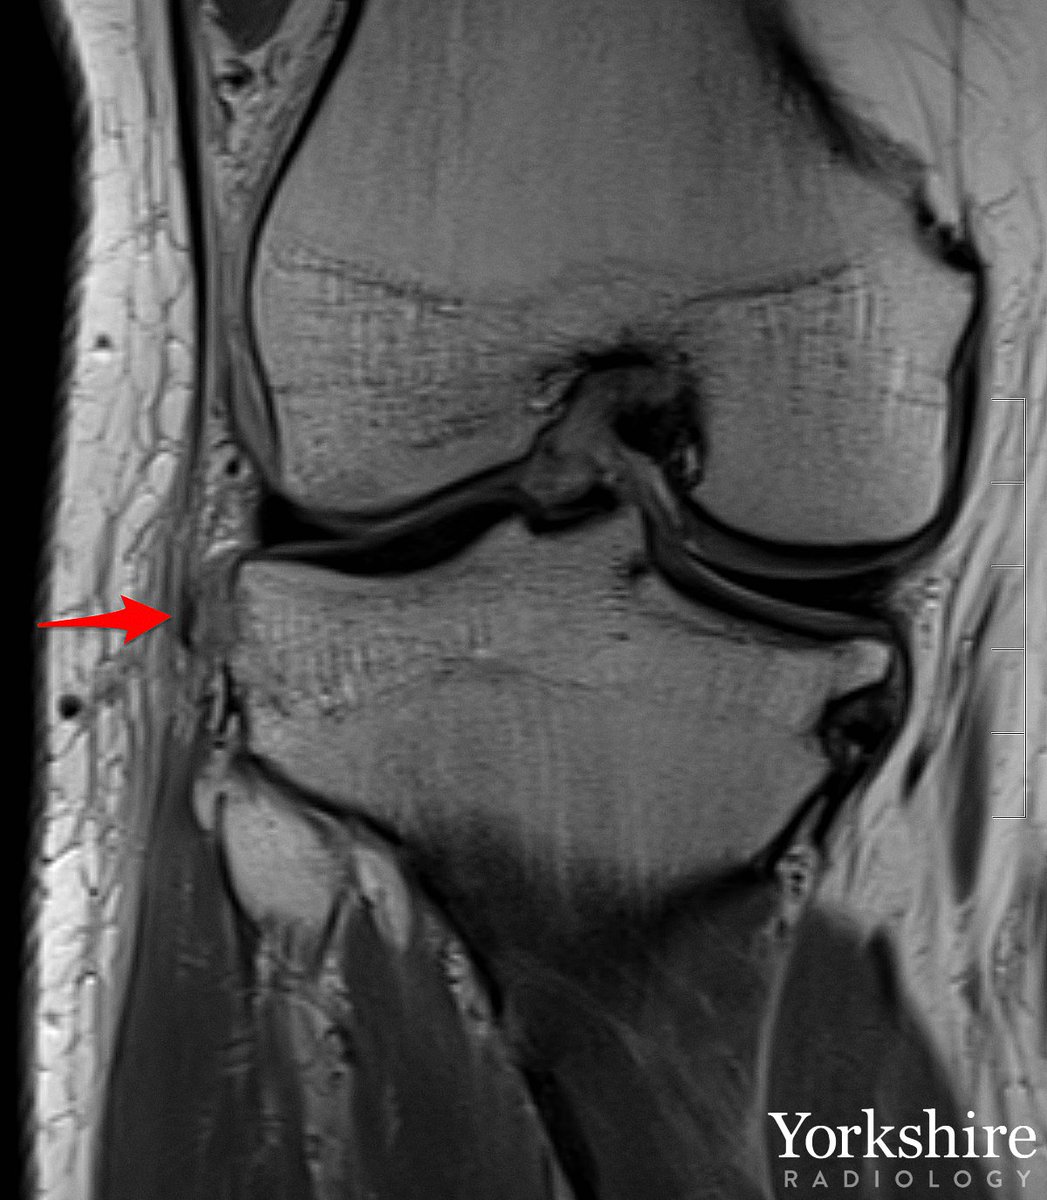

MCL injury gallery. Grade 1, 2 & 3. #orthotwitter